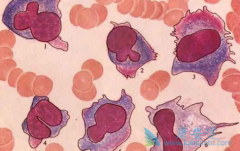

获得性血栓性血小板减少性紫癜(TTP)是由 ADAMTS13 自身抗体引起的一种危及生命的疾病。血浆置换等治疗方法能够提高生存率,但很多情况下仍难缓解。英国Scully 教授近期在 British Journal of Haematology 发表了硼替佐米用于难治性 TTP 的研究。研究者 ...